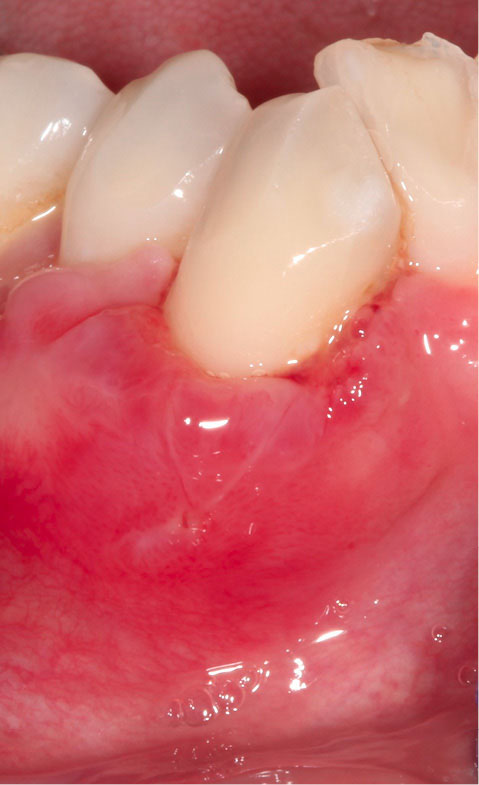

A 42-year-old Caucasian female with no significant medical history was seen at our periodontal practice for severe dental hypersensitivity at tooth #43 and extraction of nonrestorable tooth #42 (Figure 1 – at the time of initial consultation). The patient was referred from a distant area. This limited our capacity to follow up the patient for a longer period. At the initial examination, orthodontic and prosthodontic consultation was recommended to improve malocclusion and bring tooth #43 inside the alveolar housing for rehabilitation and restoration of the occlusal wear. However, the patient refused orthodontic and occlusal therapy. Written and verbal informed consent was given by the patient before the commencement of the treatment. Periodontal parameters, including probing depth, the height and width of gingival recession, bleeding on probing, the presence or absence of keratinized tissue, frenum pull, vestibular depth, mobility, and position of the tooth with regards to alveolar housing were recorded. Radiographic examination revealed early bone loss. Based on the preliminary examination, tooth #43 was classified as Miller Class III gingival recession (5 mm in height and 5 mm in width as measured by a periodontal probe). The recession was U-shaped. Reduced vestibular depth, thin biotype, and lack of keratinized tissue were noted. The tooth #43 was located out of alveolar housing. Probing depth, mobility, and bleeding on probing were all within the normal limits. Severe gingival recession (height and width of 5 mm), lack of keratinized tissue, thin biotype, shallow vestibular depth, the tooth position, the shape of the defect (U-shaped), and out-of-alveolar housing of the tooth made it a complicated case. Therefore, the patient was informed that complete root coverage was not very likely.

japid-12-90-g001

Figure 1. At the time of initial consultation, prior to periodontal therapy.